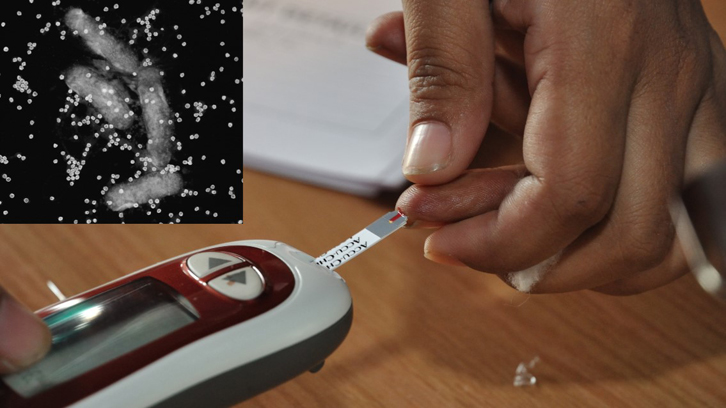

Des de fa un cert temps, s’ha replantejat l’ús de bacteriòfags, els quals són virus que infecten exclusivament als bacteris, com alternativa als antibiòtics o com a mesura complementària....